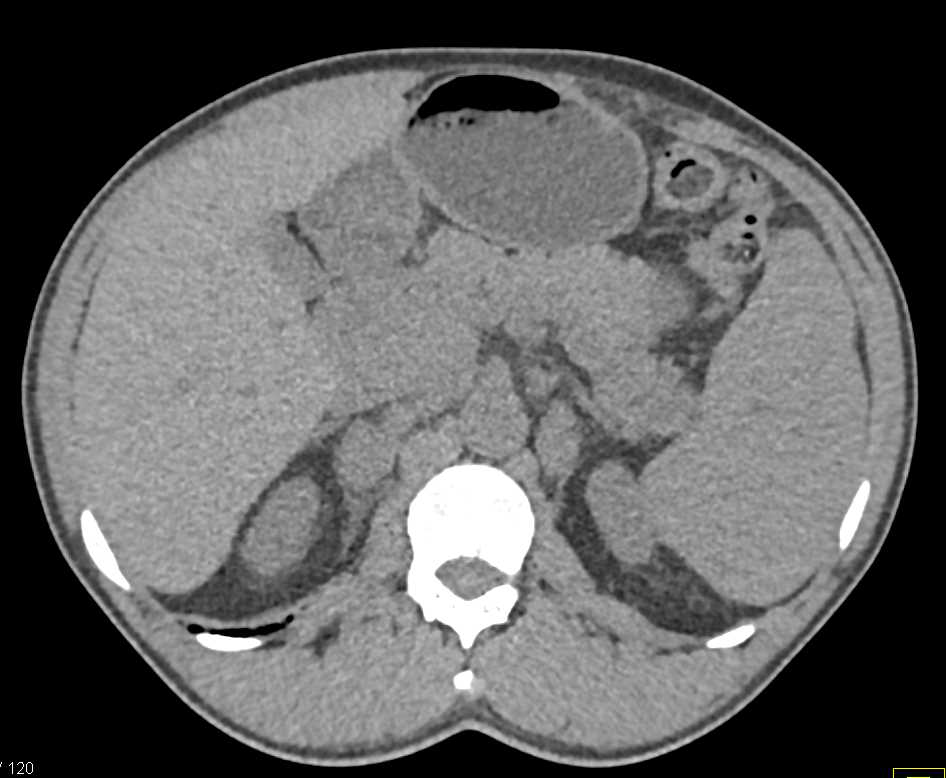

Splenic Cyst